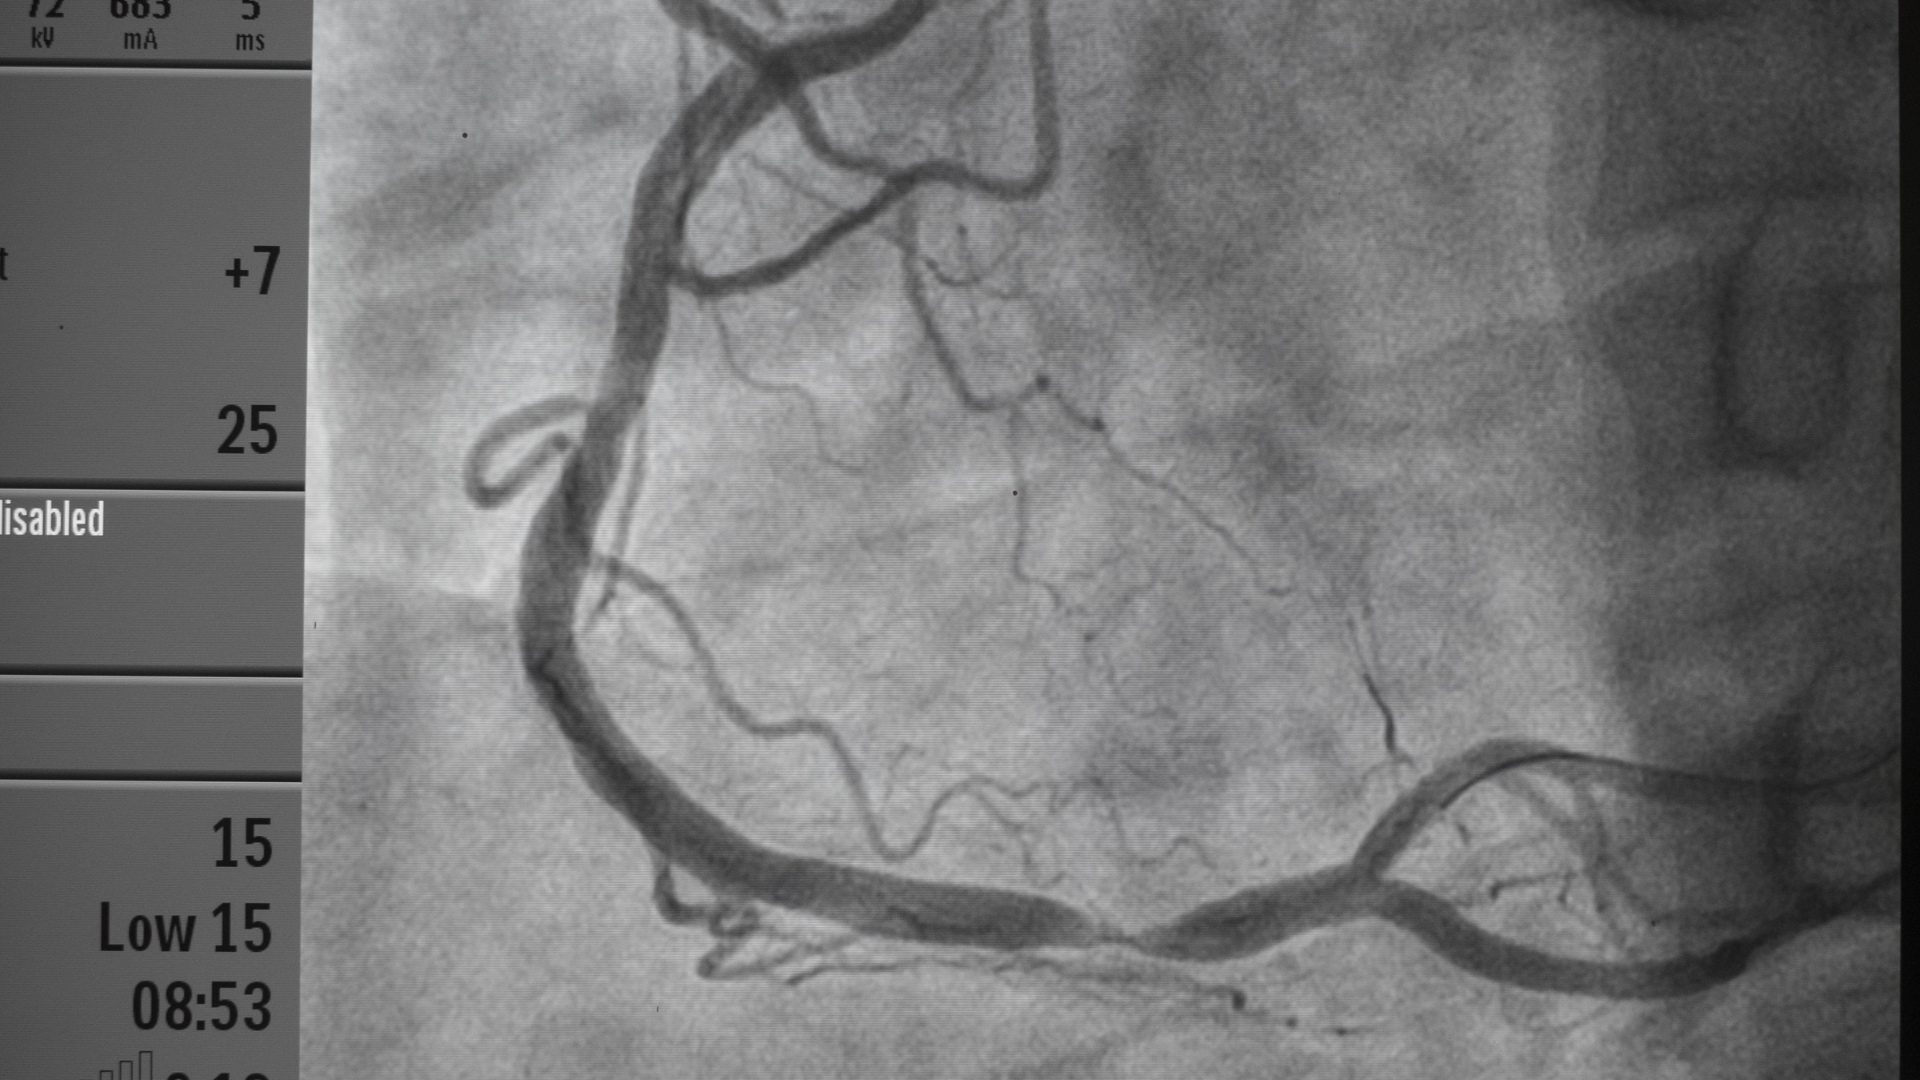

Chụp mạch vành (coronary angiography): Là tiêu chuẩn vàng để phát hiện vị trí, mức độ hẹp hoặc tắc nghẽn động mạch vành, từ đó quyết định can thiệp nong mạch hay phẫu thuật.